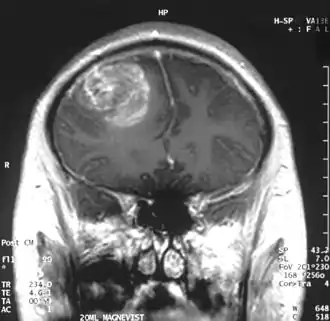

En las imágenes de TC y RM se muestra como una lesión heterogénea, de contorno irregular, que capta contraste en anillo y con un área central necrótica.

Diagnóstico por imagen y glioblastoma

La TC muestra una lesión de morfología irregular, predominantemente hipodensa y fuertemente dishomogénea, debido a la presencia de grandes áreas necróticas de más clara hipodensidad y de áreas sólidas hiperdensas. Estas últimas son la expresión de un rápido crecimiento y por lo tanto de una elevada malignidad. Son frecuentes las zonas hemorrágicas, que van desde pequeños focos a grandes áreas hemáticas que pueden cubrir toda la lesión. Es característica la morfología en "mariposa" si el tumor se asienta en ambos hemisferios a través del cuerpo calloso.

Tras la aplicación de contraste aparecen gruesos anillos alrededor de las áreas necróticas. En la RM, la parte sólida aparece hipointensa en T1 e hiperintensa en T2 con zonas de señal más elevada en las partes de mayor celularidad. Las áreas necróticas, hiperintensas en T2, pueden presentarse hipo-, iso- o hiperintensas en T1 en función del contenido proteico o de productos de la degradación de la hemoglobina. El realce tras el contraste suele ser intenso e irregular en la periferia del tumor e identifica sobre todo la componente celular "proliferativa" de la neoplasia. Son comunes las áreas puntiformes y serpiginosas de ausencia de señal de flujo, asociadas a la presencia de una neovascularización rica. Estos vasos de neoformación patológica carecen de barrera hematoencefálica, lo que explica tanto la abundante impregnación como el edema vasogénico perilesional (véase la sección anterior), debido al paso de líquido al medio extracelular.[72][73]